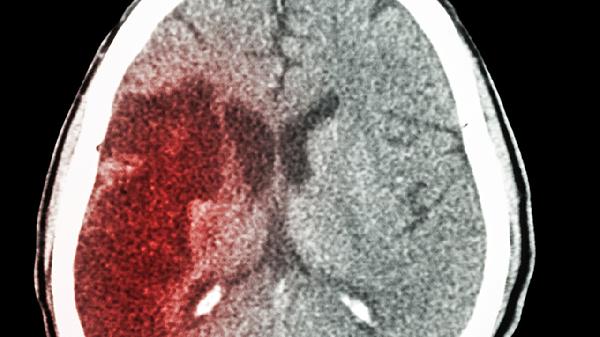

儿童脑出血可能由外伤、脑血管畸形、血液系统疾病、感染、高血压等因素引起。儿童脑出血通常表现为头痛、呕吐、意识障碍、抽搐等症状,需及时就医明确病因并接受针对性治疗。

脑血管畸形如动静脉畸形、海绵状血管瘤等可导致自发性脑出血。这类疾病可能与先天发育异常有关,通常表现为突发剧烈头痛、癫痫发作等症状。确诊需通过脑血管造影或核磁共振检查,治疗包括手术切除、介入栓塞等方法。